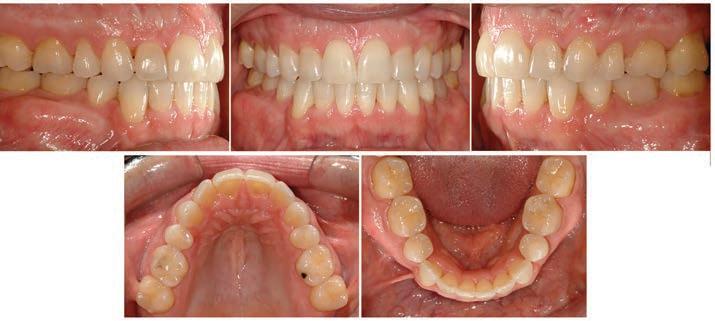

The INITIAL intraoral photographs (Figure 2) reveal a missing premolar in all quadrants except the mandibular right. There is significant crowding in the mandibular arch only. The mandibular dental midline is 2.5mm to the left of the maxillary dental midline. Tooth #20 is in buccal crossbite and rotated approximately 90 degrees. The molar relationship is Class I bilaterally, however, the canine relationship is Class III on the right side only. The mandibular right crowding, midline deviation, and right canine Class III relationship are all the result of having two premolars in the mandibular right quadrant only. In retrospect, it would have been better for this patient to have had four premolars removed as a child, one in each quadrant. Finally, there is the obvious openbite from

premolar to premolar and mildly inadequate overjet. It is worth noting that this adult patient presents with bilateral asymptomatic mandibular posterior buccal exostoses at the outset of treatment.

Figure 1: INITIAL facial photographs Figure 2: INITIAL intraoral photographs